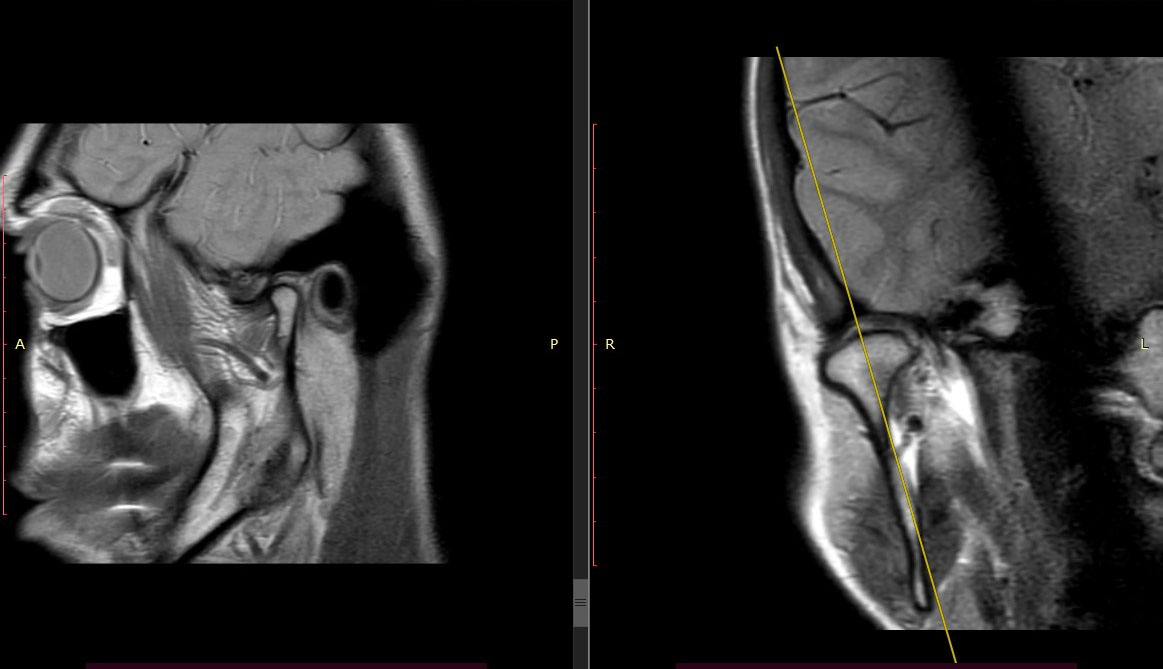

МРТ височно-нижнечелюстного сустава (ВНЧС)

МРТ височно-нижнечелюстного сустава показывает состояние не только сочленения костей, но и мягких тканей лица. На снимках видны малейшие изменения в хрящах, мышцах, челюстных костях и даже сосудах.

При МРТ ВНЧС с функциональными пробами делают отдельные снимки пациента с открытым и закрытым ртом. Также врач может попросить открывать и закрывать рот во время сканирования. Такой способ помогает оценить функциональность нижней челюсти и выяснить, что мешает ее нормальной работе.